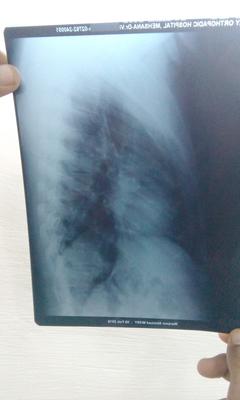

dorsal x ray

I am 29 years old. From the last one month I am having continous pain in my back. First I thought it might be muscular pain. Later I consulted Orthopaedic surgeon who diagnosed me with decreased space L4-5-S1. Plz help me what treatment should I take?

It appears that you may have six lumbar vertebrae instead of five, sometimes creating abnormal joints at the sacrum.